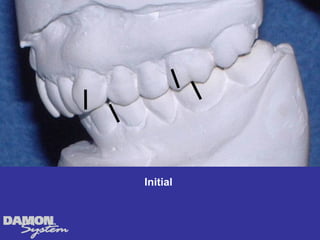

M.J. 14 yrs 6mos Class I severe crowding, deep bite, all Initial cuspids blocked out.

Initial 16 yearsโ€“ 5 months Class II, severe crowding, bilateral posterior crossbite

Treatment Planning โ€ข Ceph numbers โ€ข Model analysis โ€ข Pano X-rays โ€ข Facial analysis โ€ข Impact of growth/aging โ€ข Vestibular bone density โ€ข Tongue position/airway โ€ข How light a wire do I need to stimulate blood flow?